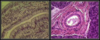

Hyaline Cartilage (specialized connective tissue)

chondrocytes in lacunae

covering bone surfaces at synovial joints, supporting the larynx, trachea, and bronchi

provides flexible support, reduces friction btwn bony surfaces

Hyaline cartilage in trachea

glassy ECM